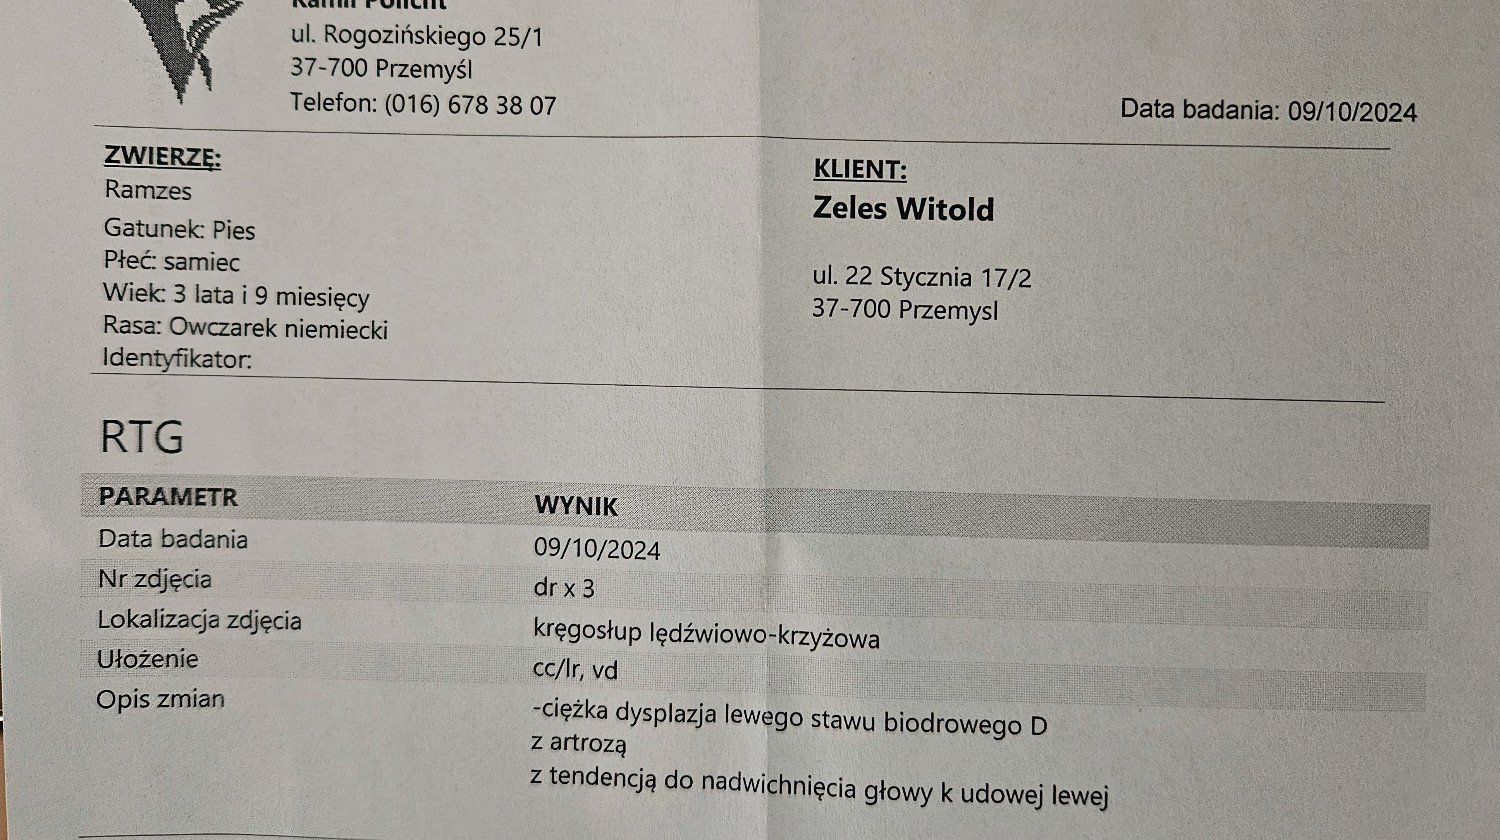

Ramzeska adoptowałem ponad pół roku temu, i nie wiedziałem że jest tak poważnie chory. Zdjęcia były wysłane do kliniki w Czechach, z której to otrzymałem telefon, że operacja będzie kosztować 4500 euro. Nie wiem ile w tym prawdy, ale pan doktor mówił że już 3 dni po operacji pies będzie normalnie funkcjonował.